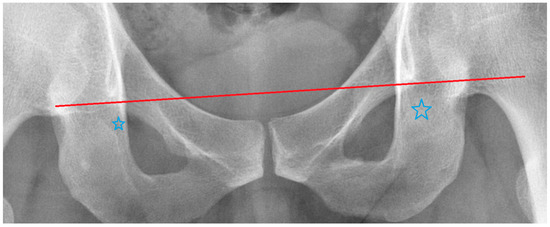

| The Outliers We Removed | Image Features |

|---|---|

| Outlier 1 of ∠RSC | Uneven protrusions on bilateral iliac crests. |

| Outlier 2 of ∠RSC | Normal |

| Outlier 1 of ∠RBI | Poor image quality, but borders of the pelvic landmarks are still visible. |

| Outlier 2 of ∠RBI | Right side femur fracture without femoral head dislocation. |

| Outlier 1 of ∠RIT | Asymmetrical teardrop shapes on both sides. |

| Outlier 2 of ∠RIT | Asymmetrical teardrop shapes on both sides. |

| Outlier 1 of ∠RUO | Normal |

| Outlier 2 of ∠RUO | The obturator foramen is slightly distorted on the image. |

| Outlier 1 of ∠RLO | Normal |

| Outlier 2 of ∠RLO | Normal |